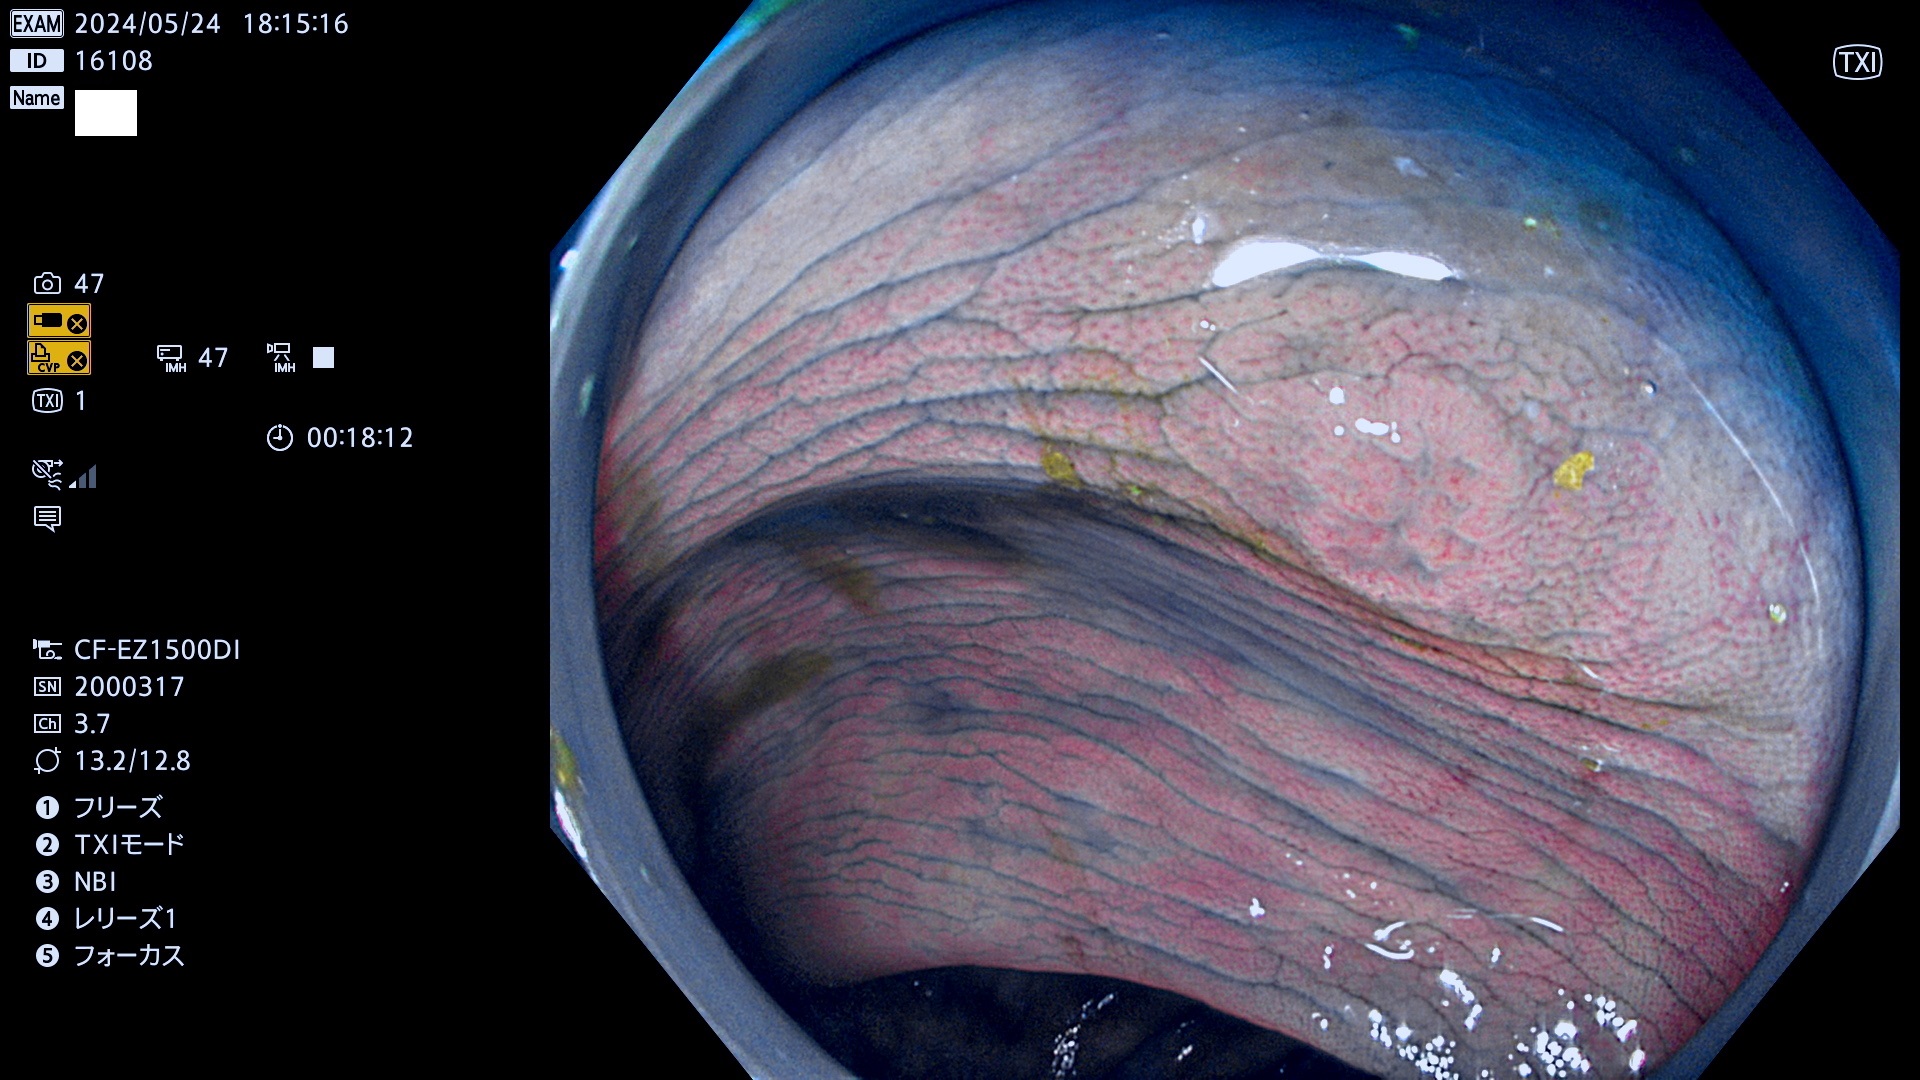

表面型腺腫(Flat Adenoma)の中で、完全に平坦な物をUb、陥凹している物をUcと呼びます。平坦隆起型(Ua)よりも、発見が難しく危険な病変です。

ビランと鑑別の難しい陥凹型腺腫